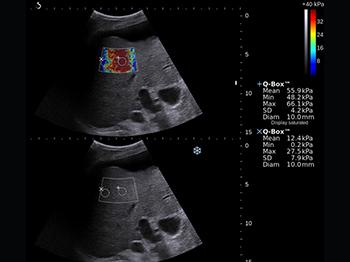

- Эластография компрессионная.

- Эластография - опция оценки эластичности ткани с программой анализа (компрессионный метод)

Примеры сканирования Apogee 5500